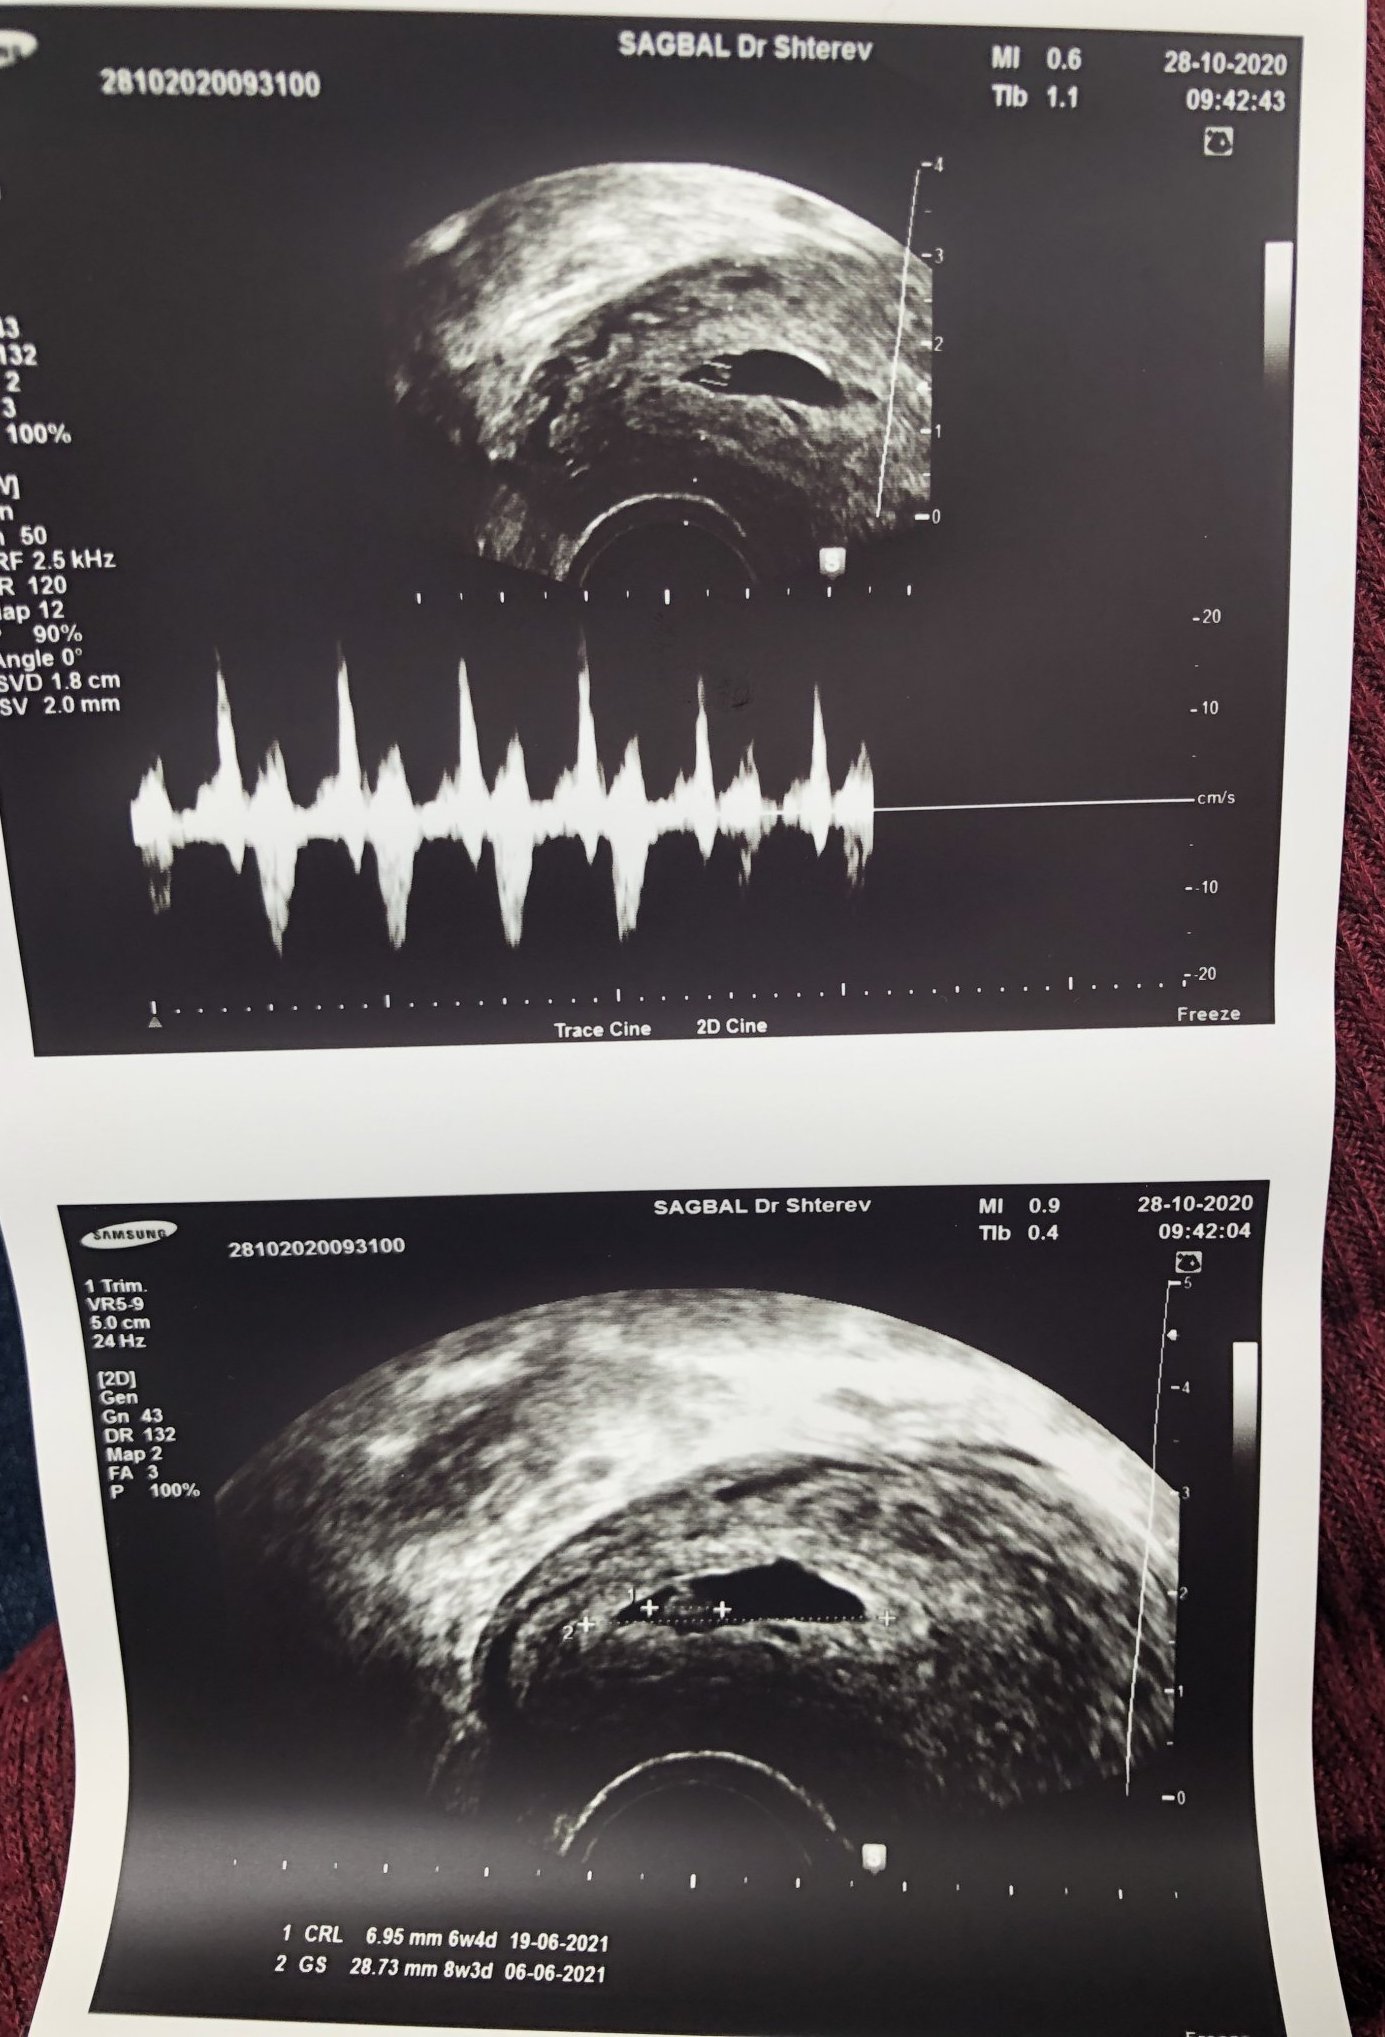

Моят сак също е малко по-дълъг, каза ми, че е възможно бременността да е була двуплодна и затова да е такъв, но сега има само едно бебче.